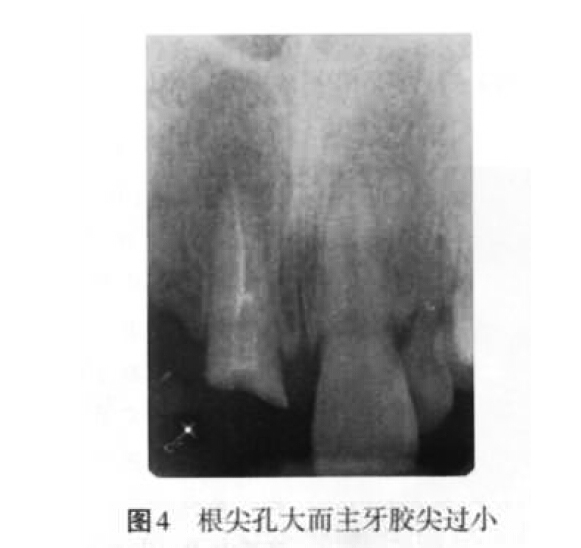

(1)欠充原因:當(dāng)根管預(yù)備不足、根管工作長(zhǎng)度測(cè)量不準(zhǔn)確(圖 3)、主牙膠尖選擇不合適、根充技術(shù)選擇不當(dāng)以及術(shù)者操作不當(dāng)時(shí),均可以導(dǎo)致欠充發(fā)生。